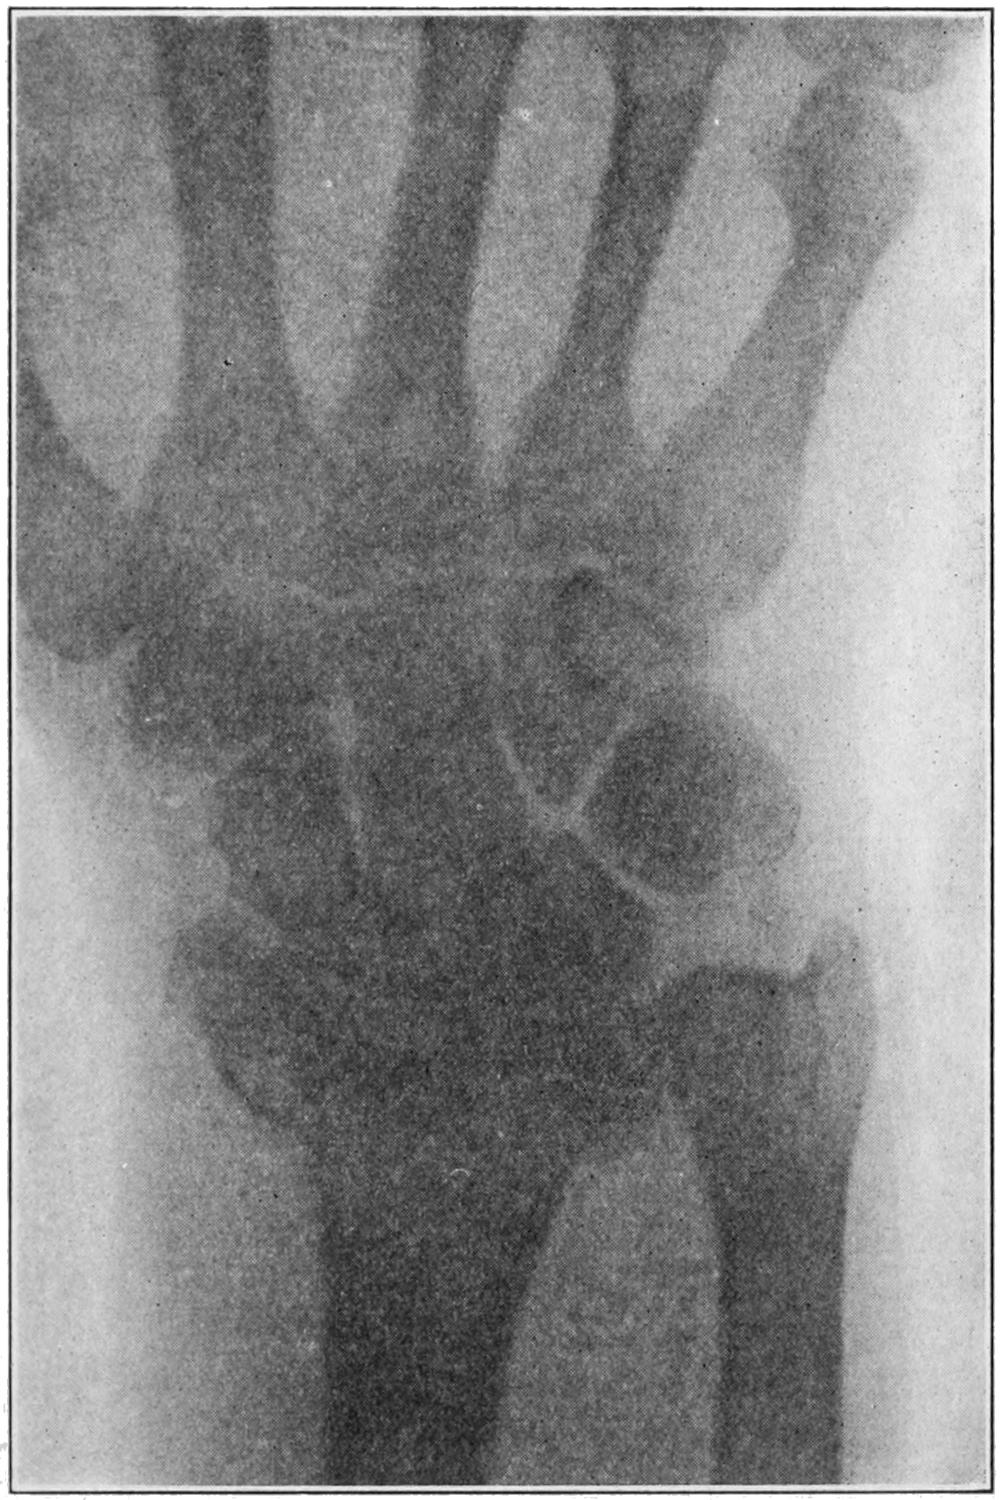

Fig. 1

Congenital hypertrophy: gigantism of both lower extremities. (Case of Dr. Graefe [Sandusky].)